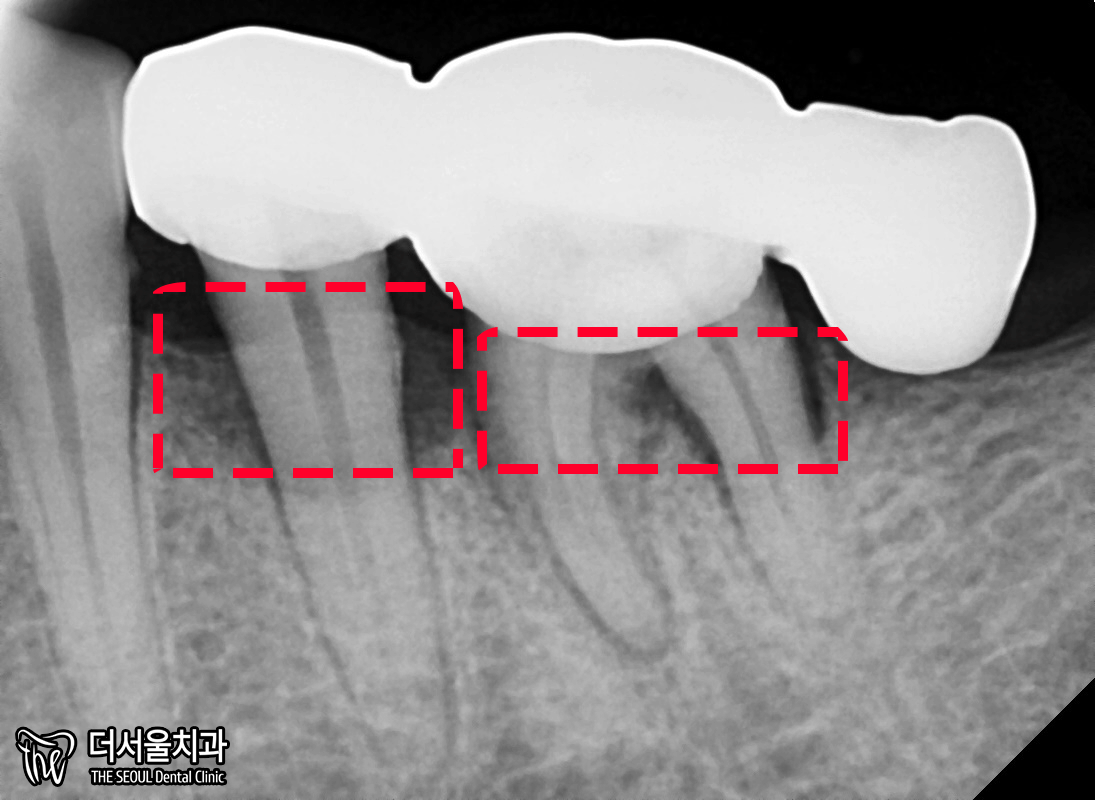

좀 더 자세히 보여드리겠습니다.

뿌리 쪽을 보면 시커멓죠?

염증이 있는 것을 알 수 있습니다.

이러니 흔들림이 나타날 수밖에 없구요.

아래 왼쪽 어금니 부분에도 마찬가집니다.

뿌리 끝은 아니지만,

중간 즈음으로 검게 변한 것을 볼 수 있습니다.